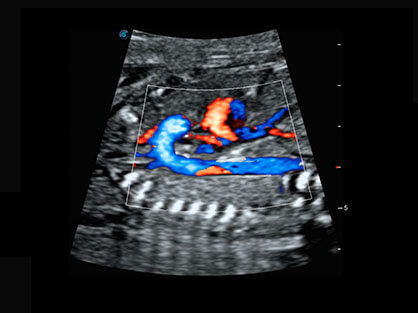

宽频带腹部凸阵探头和腹部容积探头、大角度腔内探头和腔内容积探头、独特的生殖专用曲柄探头,为妇产应用提供全面诊疗方案。

卵泡结构的自动识别和测量,可显示多组测量数据。

大角度腔内容积探头,可完整包络子宫及盆底结构,充分展示组织结构毗邻关系。